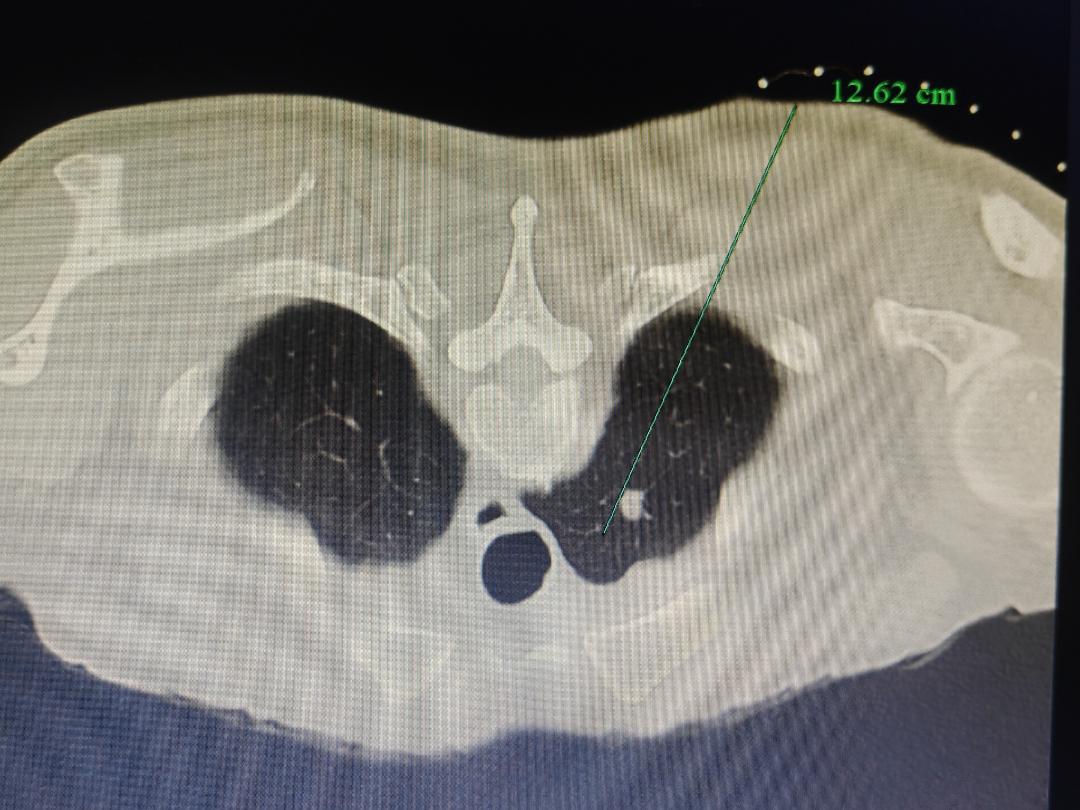

1.精准定位:医生通过CT影像锁定肿瘤位置,像导航一样精准规划“进攻路线”。

2.细针穿刺:用一根比笔芯还细的针,避开重要血管和器官,直达肿瘤“老巢”。